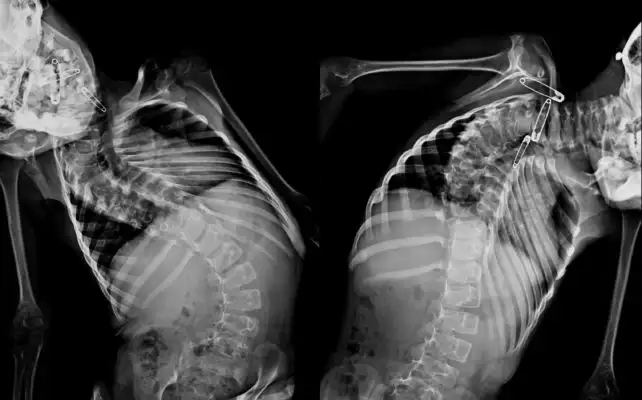

Six children in India with complex spine deformities are standing straight and healthy today thanks to a mission trip led by surgeons from Cincinnati Children’s.The surgical team was headed by renowned spine surgeon Alvin Crawford, MD, and was organized by Shital Parikh, MD, a surgeon in our Division of Orthopedic Surgery.The team visited Parikh’s hometown